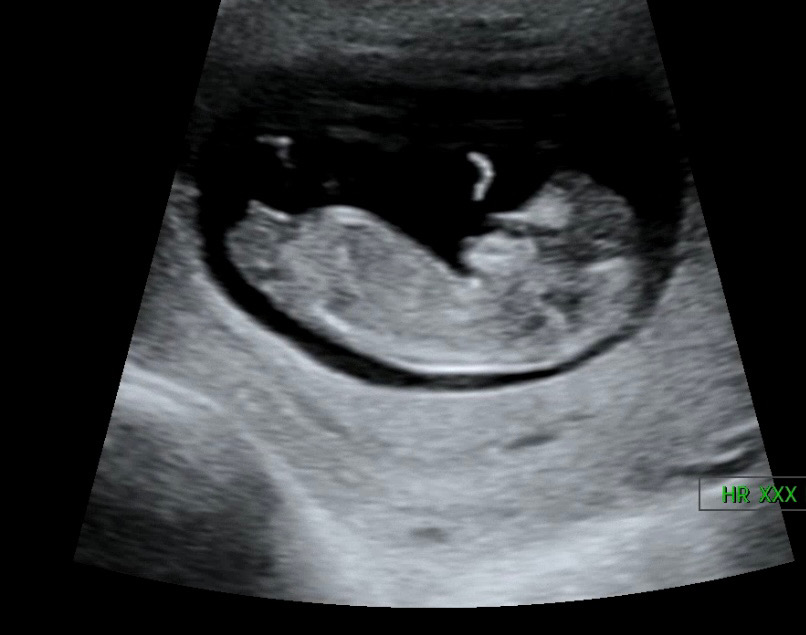

안녕하세요 12주차 진입했습니다! 혹시 저 배 아래 뾰족한게 다리뼈 일부가 찍힌걸까요? 아님 생식기 부분이 찍힌걸까요? 초음파 잘 보신다면 의견 부탁드리겠습니다 😁

생식기 맞아요! 각도도 척추랑 일직선이고 끝이 갈라지면 딸 확률이 높다네요